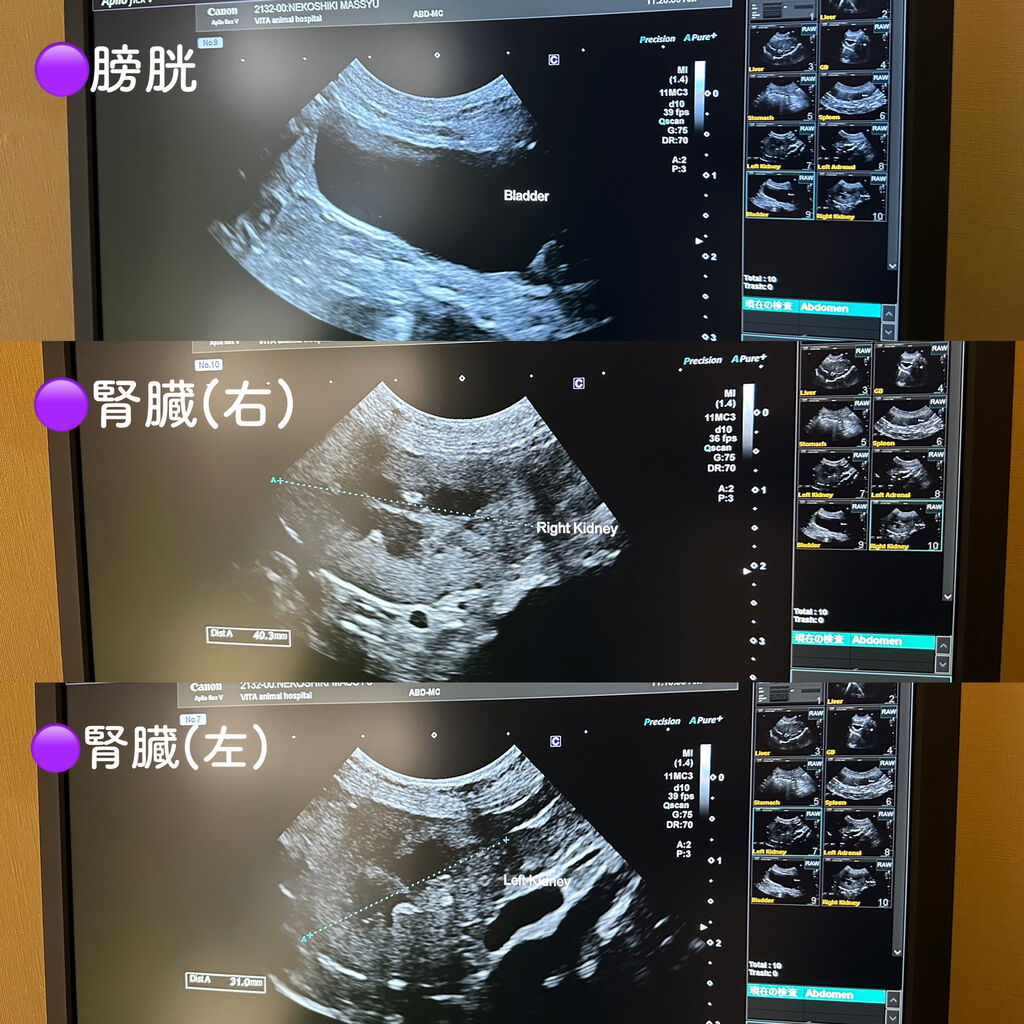

レントゲンや超音波検査もやりました

▼超音波

先生いわく、特に異常はないそうです